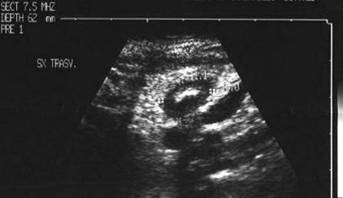

Barbat de 57 ani. Tiroida de dimensiun marite, de consistenta mult marita, dureroasa la palpare, cu suprafata neregulata cu senzatie de nodularitate. Ecografia: cresterea volumului; marginile lobilor rau definite; structura este intens neomogena cu alternanta de arii hipoecogene de edem si altele intens ecogene, cu aspect pseudonodular. Examene de laborator: moderat hipertiroidism; indici de fibroza mult ridicati. Citoaspiratie -celule gigante de tip Langhans, celule inflamatorii de tip acut si cronic, numerosi fibroblasti.